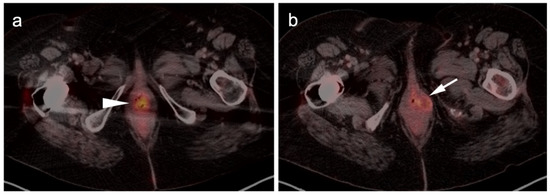

- Falch, C.; Mueller, S.; Kirschniak, A.; Braun, M.; Koenigsrainer, A.; Klumpp, B. Anorectal malignant melanoma: Curative abdominoperineal resection: Patient selection with 18F-FDG-PET/CT. World J. Surg. Oncol. 2016, 14, 185. [Google Scholar] [CrossRef] [Green Version]